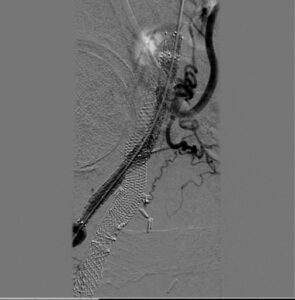

Figure 3. Angiographic results post stent deployment in the subintimal space.

Access was gained in the left common femoral artery. We advanced a 7-frech Pinnacle 65cm sheath up and over to the right CFA. We were able to probe the vessel outside the previously occluded stent and gain access to the true lumen of the vessel beyond the occluded stent in the distal right SFA. A number of wires were used, including stiff Glidewire and an Amplatz wire. The stiff straight guidewire was used, along with a vertebral catheter, QuickCross catheter, and Trailblazer 0.035 catheter. We dilated the vessels with a 3.5mm Nanocross balloon. We then dilated the right superficial femoral artery with a 6mm balloon, followed by a 7mm balloon. After dilation, right SFA occlusion went from 100% to 60% severe recoil. We deployed 6×120 and 6×80 Supera stents, overlapping them with care to improve stacking of the stents to optimize radial strength. This was in the mid to distal SFA. The completion angiogram revealed a good result, with less than 20% residual stenosis at the SFA post double-barrel stenting. Patient tolerated the procedure well and was kept on DAPT.